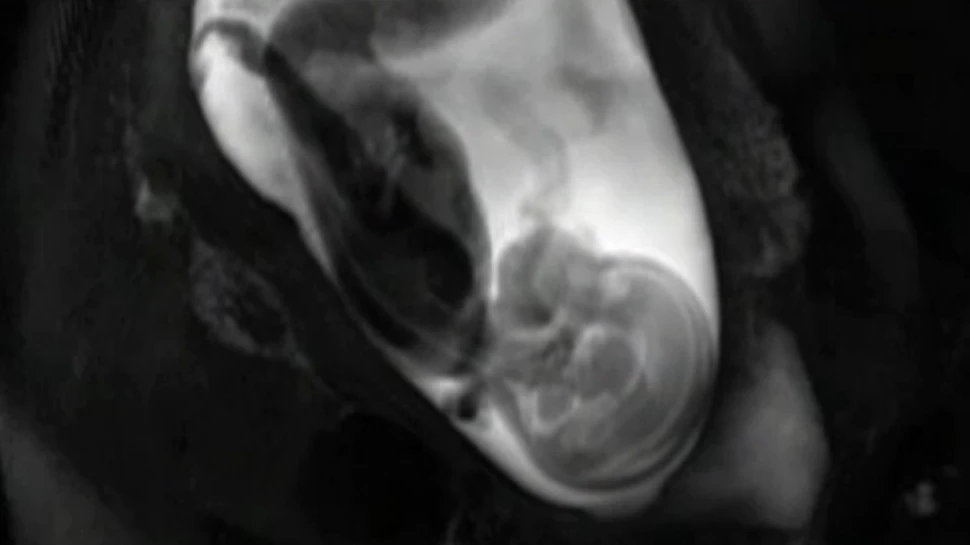

Folosind tehnici de imagistică fMRI, oamenii de ştiinţă au reuşit să creeze un video în care să arate cum se dezvoltă creierul unui făt, în uterul mamei. Mai exact video-ul arată cum se formează conexiunile din creier, iar specialiştii susţin că astfel de cercetări ar putea duce la crearea unor tratamente pentru autism sau schizofrenie.

Imaginile au fost surprinse de Moriah Thomason de la  Wayne State University, din Detroit. Împreună cu echipa sa de cercetători,  Thomason  a folosit rezonanţă magnetică funcţională pentru a scana creierele a 25 de feţi care aveau între 24 şi 38 de săptămâni de viaţă intrauterină. Fiecare scanare a durat, în medie,  10 minute  iar specialiştii au păstrat pentru video doar imaginile în care feţii au stat nemişcaţi.

Scanările au fost realizate pentru ca cercetătorii să poată arunca o privire asupra două caracteristici bine înţelese ale creierului în curs de dezvoltare: distanţa dintre conexiunile neuronale şi momentul în care ele se dezvoltă. Aşa cum era de aşteptat, de la o săptămână la alta, cele două jumătăţi al creierului fetal formau conexiuni mai dense şi mai numeroase. Cele mai vechi conexiuni tind să apară în mijlocul creierului, pentru ca ulterior ele să extindă pe măsură ce creierul se dezvoltă.